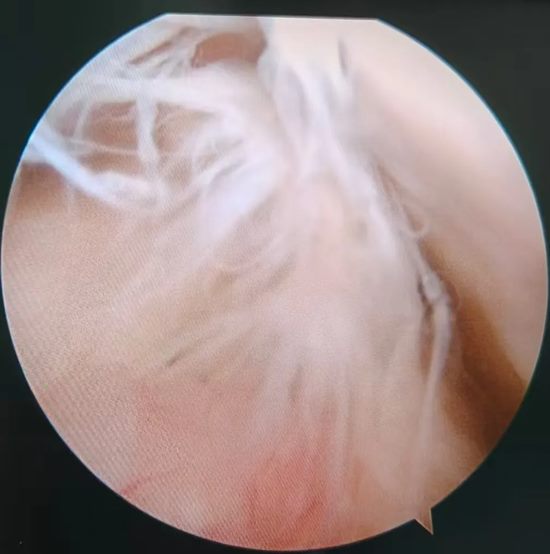

640_副本

术中关节镜探查的断裂的前交叉韧带

"手术全程在关节镜直视下操作,视野清晰,能最大限度保护周围正常组织,出血少、感染风险低。"徐明杰主任介绍,术后结合个体化康复方案,患者第二天即可扶拐下地,预计数月后能逐步恢复运动能力,在康复医学科带领下,患者仅仅2-3天膝关节就可屈曲90度,这在自体肌腱重建交叉韧带上是不可能办到的。